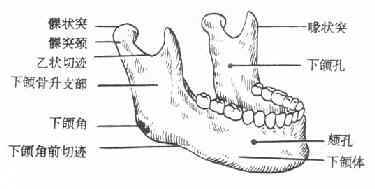

下颌骨(Mandible)

下颌骨分为体部及升支部,两侧体部在正中联合。下颌升支部上方有两个骨性突起,在后方者称为髁状突,在前方者称为喙突(肌突),两者之间的凹缘称为乙状切迹。升支部后缘与下颌骨下缘相交处称为下颌角,升支部内侧面中部有一个孔称下颌孔,此孔在下颌骨内向下向前延伸的管道,称下颌骨。下颌管在第一、第二前磨牙牙根之间向外穿出一孔,称颏孔。下牙槽神经、血管从下颌孔进入下颌管向前走行,在颏孔处分出颏神经及血管(图1-12)。

图1-12 下颌骨

由于下颌骨在髁状突颈部、下颌角部、颏孔部、正中联合部等处的结构比较薄弱,故外伤时常易发生骨折。